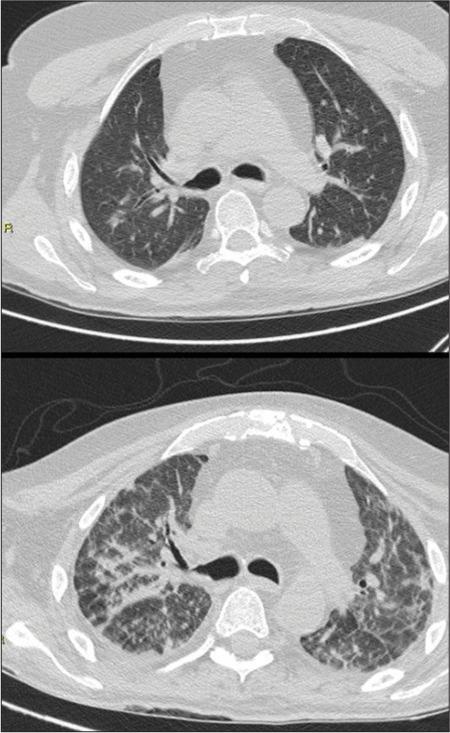

COVID-19: Correlation between HRCT findings and clinical prognosis and analysis of parenchymal pattern evolution.

Severe acute respiratory syndrome - coronavirus 2 (SARS-CoV-2) is a single-stranded positive ribonucleic acid virus of the coronaviridae family. The disease caused by this virus has been named by the World Health Organization coronavirus disease 19 (COVID-19), whose main manifestation is interstitial pneumonia. Aim of this study is to describe the radiological features of SARS-CoV-2 infection in its original form, to correlate the high-resolution computed tomography (HRCT) patterns with clinical findings, prognosis and mortality, and to establish the need for treatment and admission to the intensive care unit.

Our results confirm the role of radiology and, in particular, of chest HRCT as a technique with high sensitivity in the recognition of the most peculiar features of COVID-19 pneumonia, in the evaluation of severity of the disease, in the correct interpretation of temporal changes of the radiological picture during the follow-up until the resolution, and in obtaining prognostic information, also to direct the treatment.

Chest computed tomography cannot be considered as a substitute for real-time - polymerase chain reaction in the diagnosis of COVID-19, but rather supplementary to it in the diagnostic process as it can detect parenchymal changes at an early stage and even before the positive swab, at least for patients who have been symptomatic for more than 3 days.